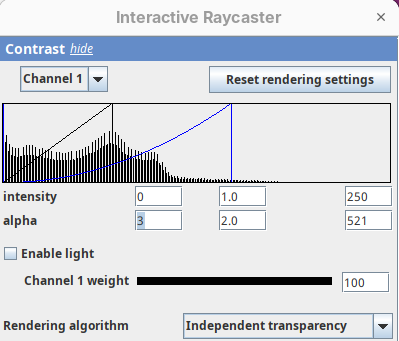

- Set the

minto0, for now. - Then, change the

maxto250.

The brightest parts of the rendering will become all white. It is so bright that we can no longer resolve details of the surface. We are losing information and also do not want that.

- Set the

maxto500.

Note that when you change an intensity value, the min/max black line in the histogram moves. You can also grab the line and move it manually to change the values.

The blue line represents the alpha values. In 3D rendering, a pixel has a transparency value linked to its intensity. The alpha min defines the value for full transparency and the max the value for full opacity.